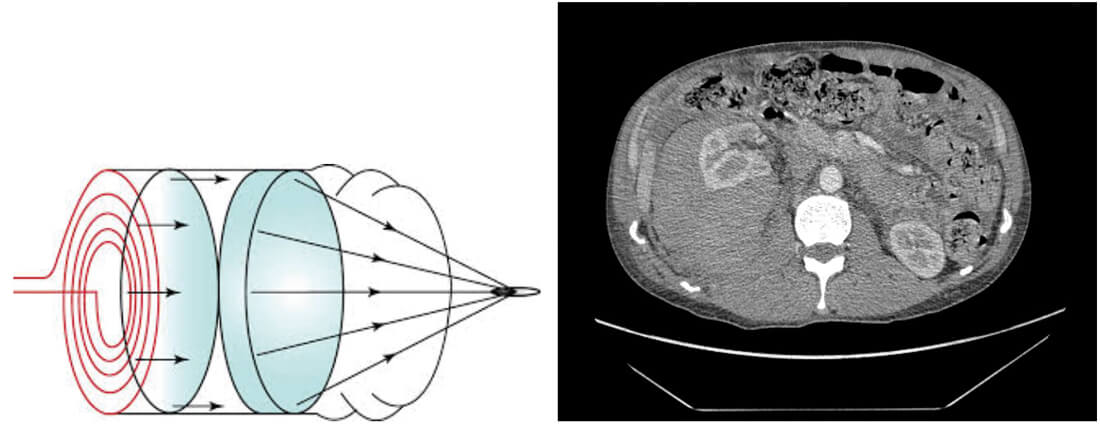

- What are the three types of lithotripter in use currently for shock wave lithotripsy (SWL), and which is illustrated by the schematic in the image?

- What does this axial CT scan image show? What complications can occur after SWL?

Electrohydraulic, electromagnetic and piezoelectric. The image shows a schematic representation of an electromagnetic lithotripter.

The image shows a large right perinephric haematoma in a patient who ultimately required angioembolisation. Other complications include pain, ureteric colic, obstruction, steinstrasse, haematuria, urinary tract infection / sepsis, renal injury, bruising, failure, need for repeat treatment, stone recurrences and intolerance of treatment or failed targeting leading to incomplete treatment.